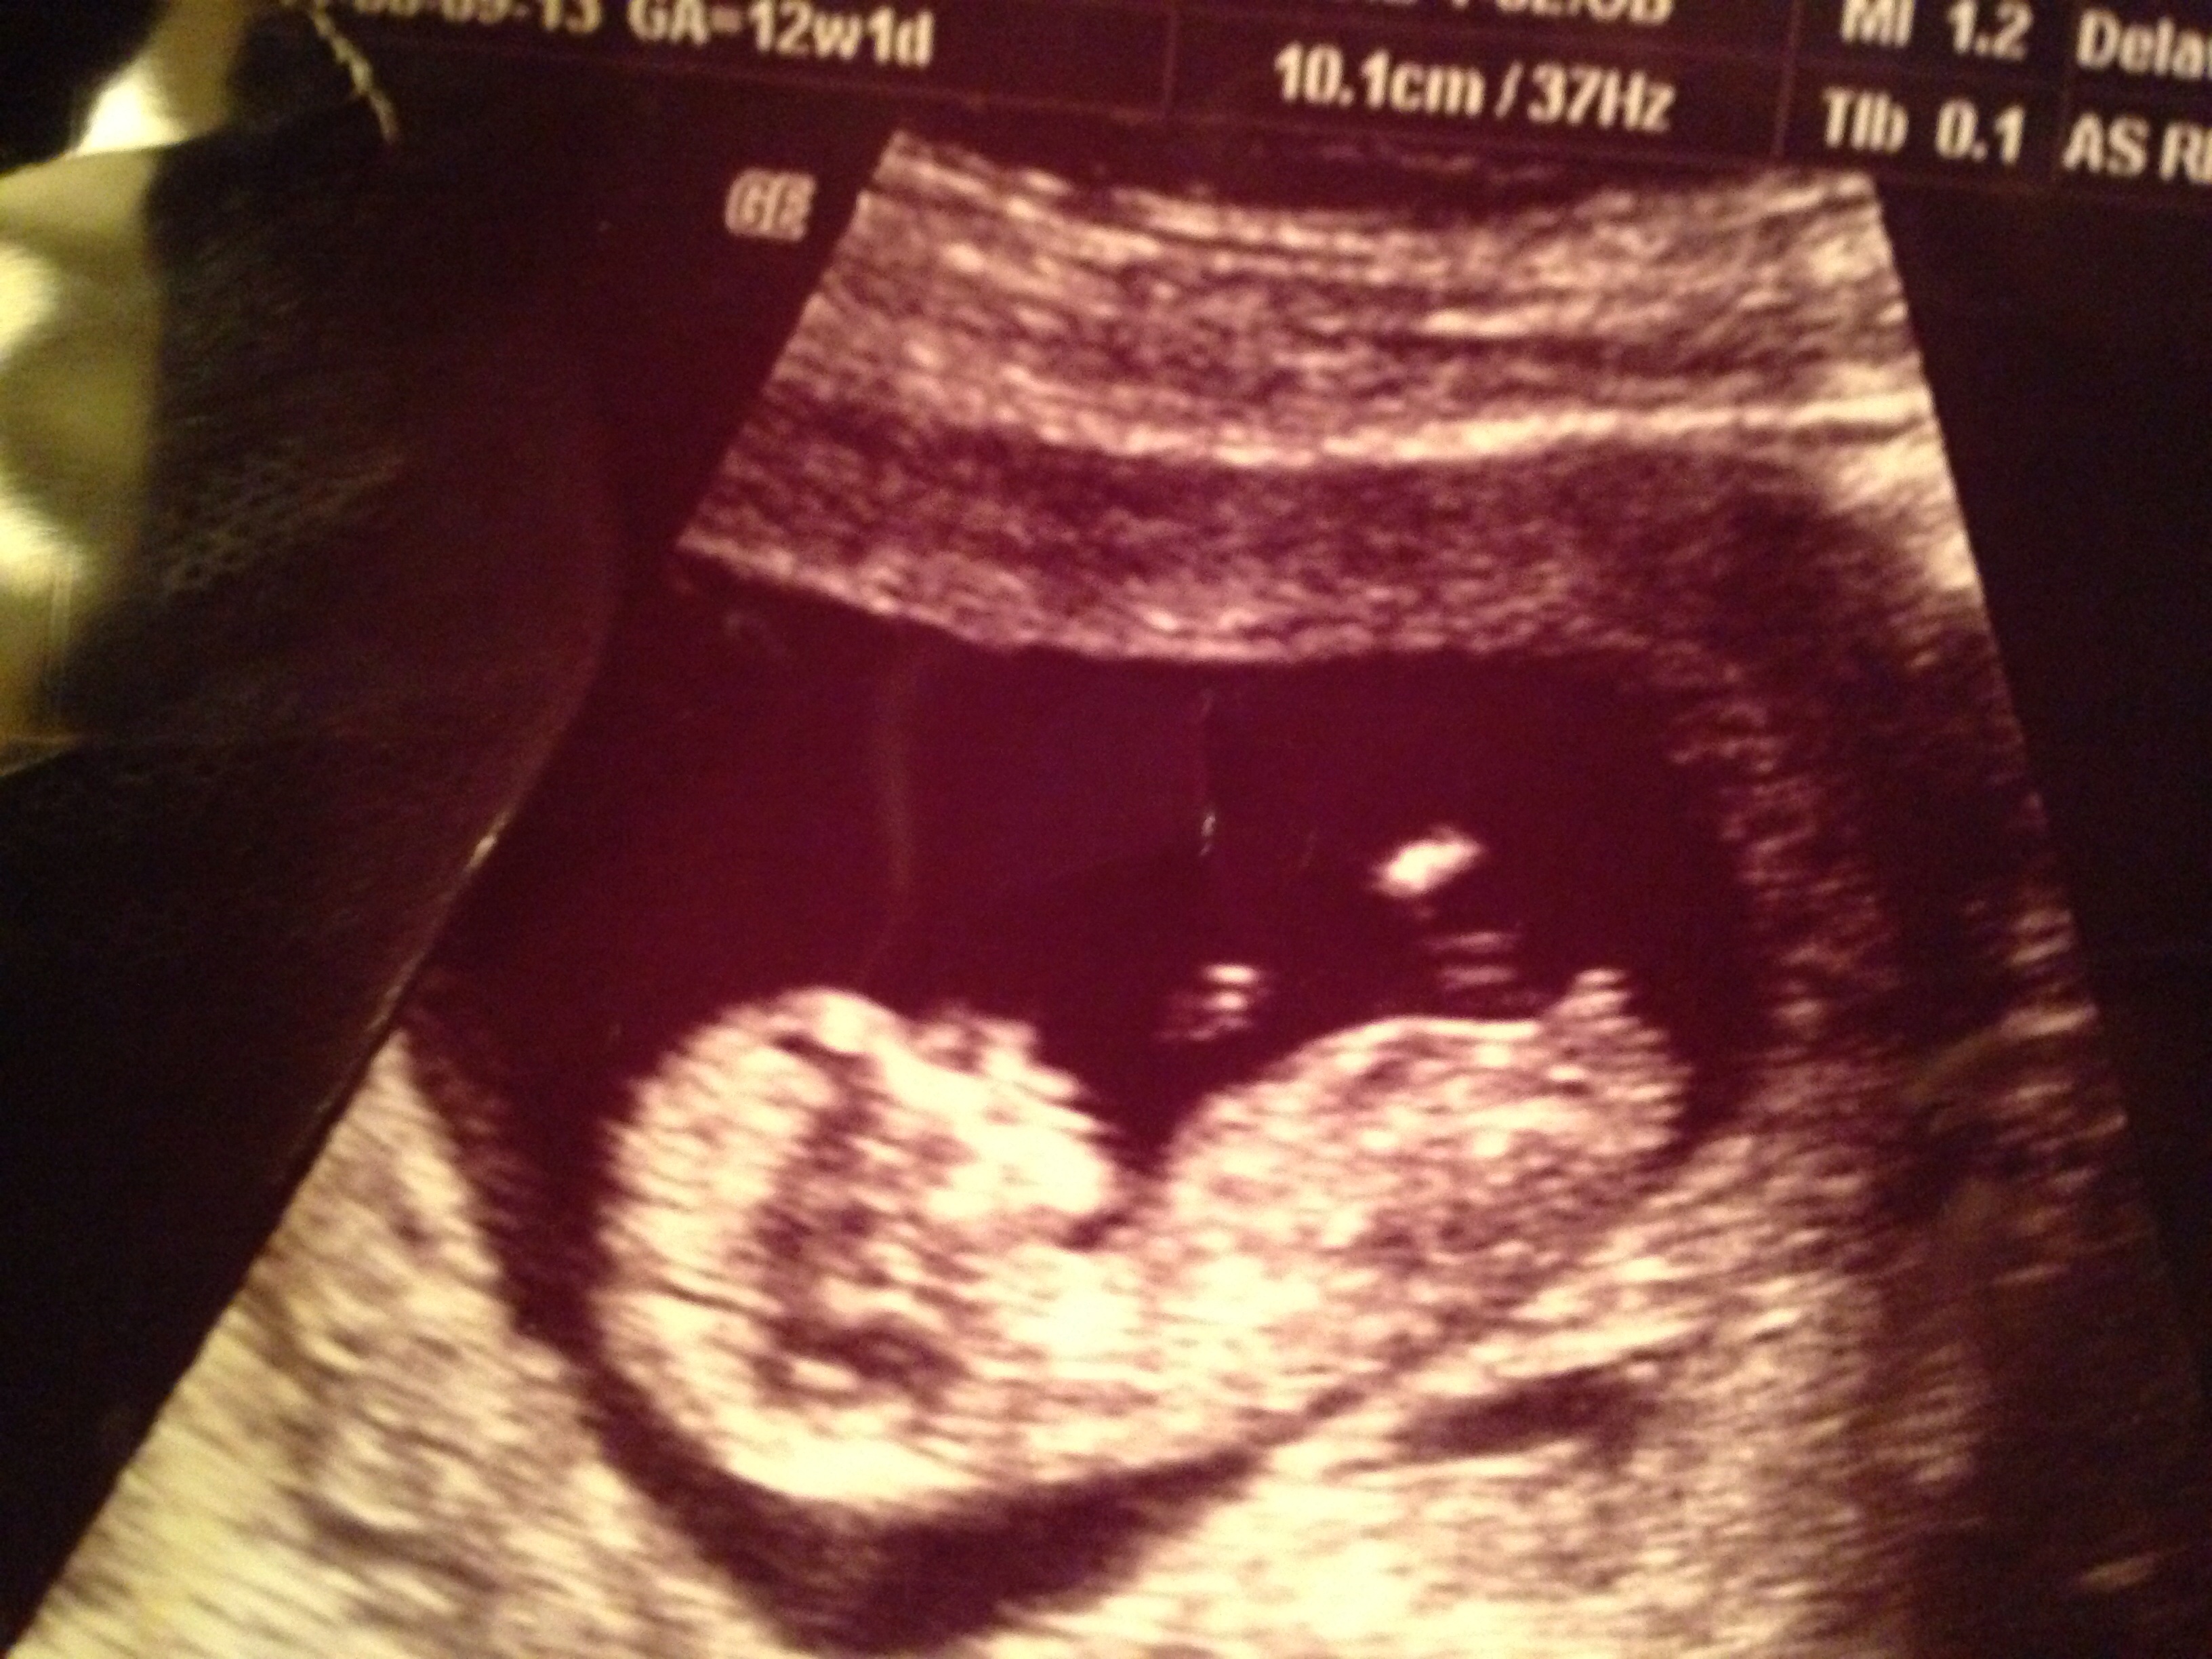

Hi! I'm totally new here, and am dying to know thoughts on the sex of my third baby!

I have a couple different US pics that look totally different!

Thank you!!Attachment 19654Attachment 19656Attachment 19655Attachment 19654Attachment 19656Attachment 19655Attachment 19654Attachment 19656Attachment 19655